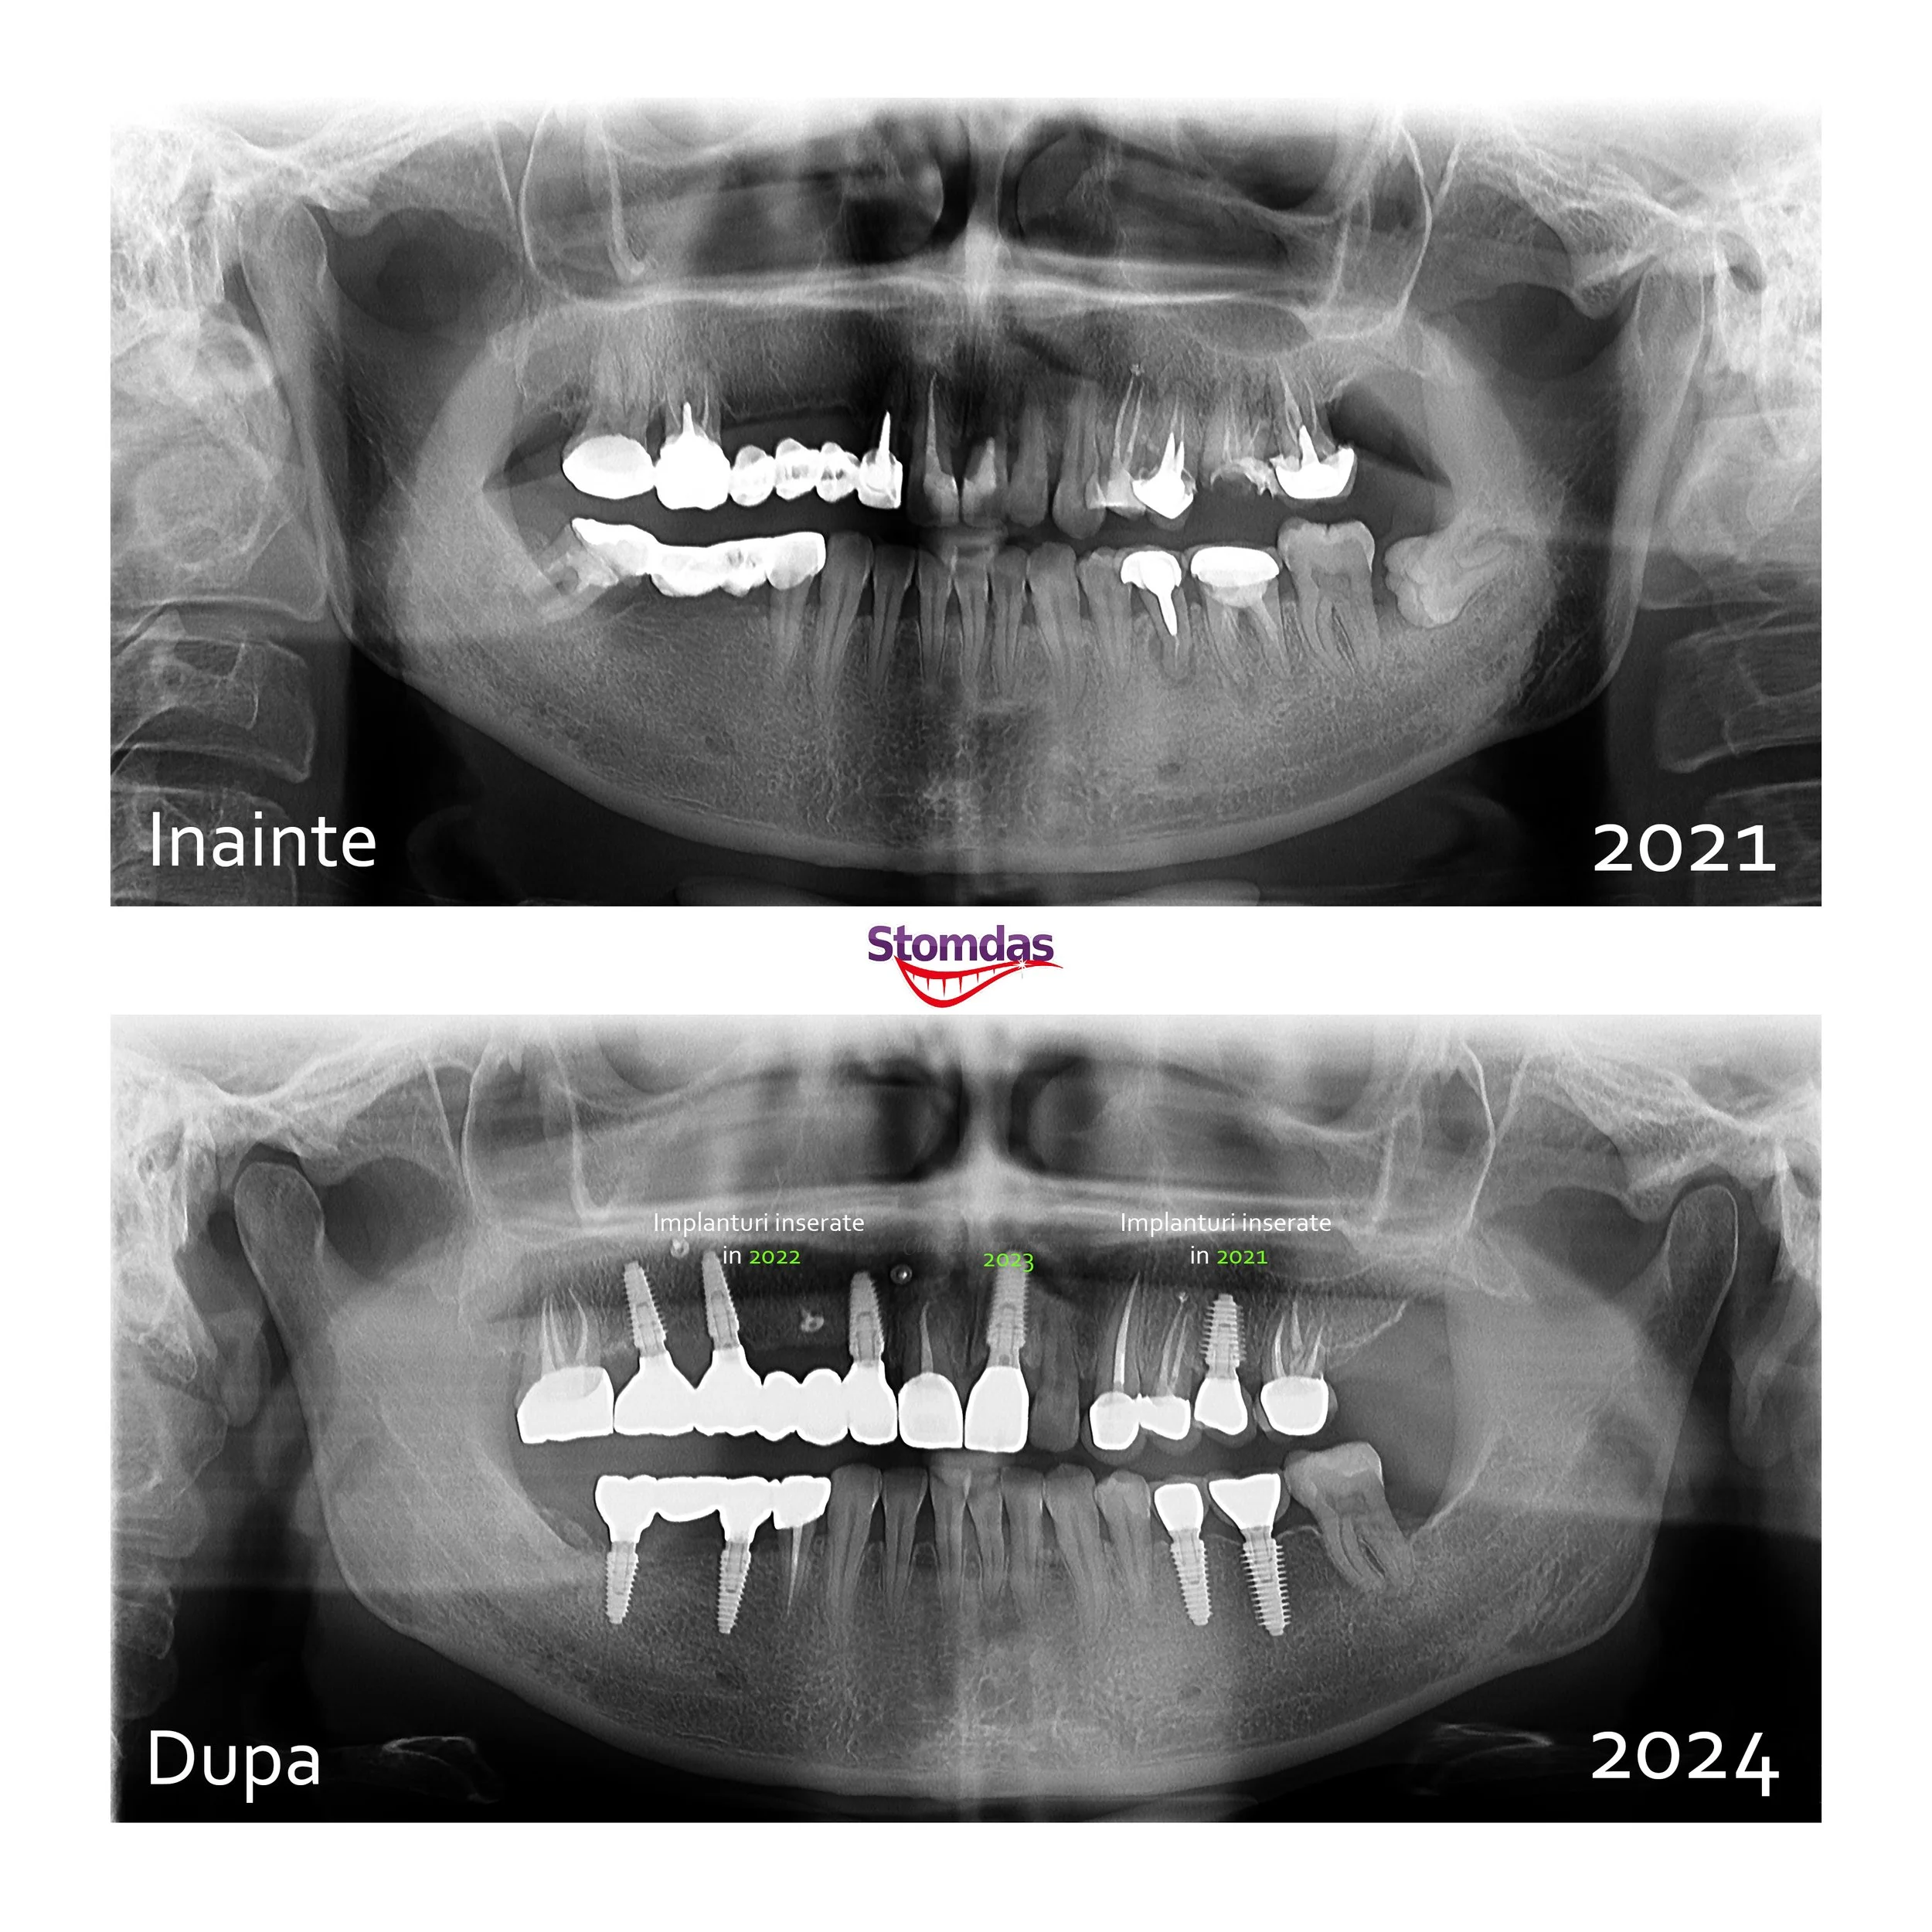

IMPLANTOLOGIE